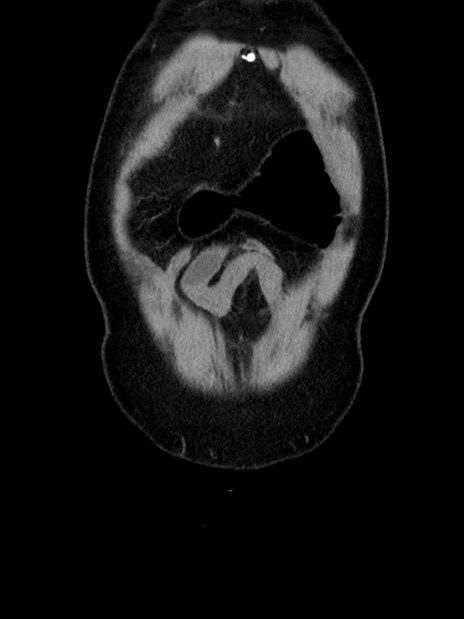

症例35(冠状断像)

横断像